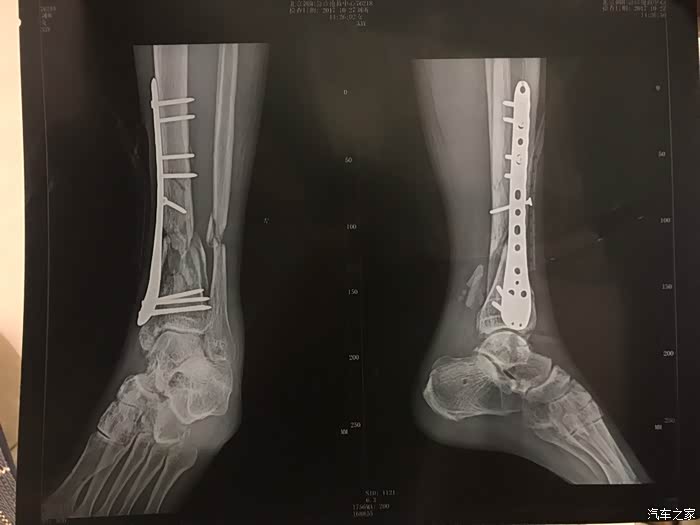

左胫腓骨远端开放粉碎性骨折

10个月,3次手术,1年康复,房贷和失业让我不得不把我的821卖掉,为此我哭了3天,不愿意面对,雪上加霜的是爸爸妈妈不允许我再次骑车了,长这么大从来没有见过爸爸哭,在医院里,爸爸陪我哭的声嘶力竭的样子,我的确也不想再次经历了

拆完还是可见腓骨连接处的脆弱,所以我平时要很小心

第三次是植骨手术,与第二次间隔了7个月,我的右胯骨又挨了一刀,取出来的骨头填补了我长不上腿骨,自此腿部拼图完成